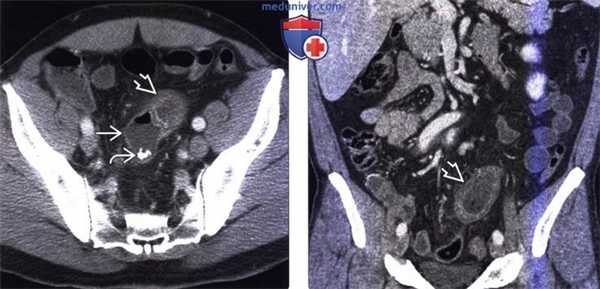

(Слева) На аксиальной КТ определяется дилятация дистального сегмента тонкой кишки и утолщение ее стенки . Расположенный рядом слепо заканчивающийся «мешок» представляет собой дивертикул Меккеля и содержит кальцинированный энтеролит в своих задних отделах. Во время операции подтвердилось воспаление дивертикула Меккеля.

(Справа) На корональной КТ (реформатированное изображение, тот же самый случай) визуализируется воспаленный сегмент тонкой кишки? где произошла обструкция, вплотную прилежащий к дивертикулу Меккеля.

3. КТ при дивертикуле Меккеля:

• Наличие в правом нижнем квадранте слепо заканчивающегося «кармана» с плотностью, соответствующей стенке кишки

• В просвете дивертикула могут определяться кальцифицированные энтеролиты

• Имеется связь между дивертикулом и просветом тонкой кишки

• Воспаление дивертикула Меккеля:

о Наличие слепо заканчивающегося «кармана», а также жидкости, газа, либо включений в виде частиц

о При воспалении дивертикула происходит утолщение его стенки и прилежащих отделов тонкой кишки:

- Стенка кишки накапливает контраст при КТ с контрастным усилением

о Определяется инфильтрация брыжеечной жировой клетчатки, жидкость, возможно также наличие узлов

о Может наблюдаться частичная либо полная обструкция тонкой кишки:

- А также инвагинация